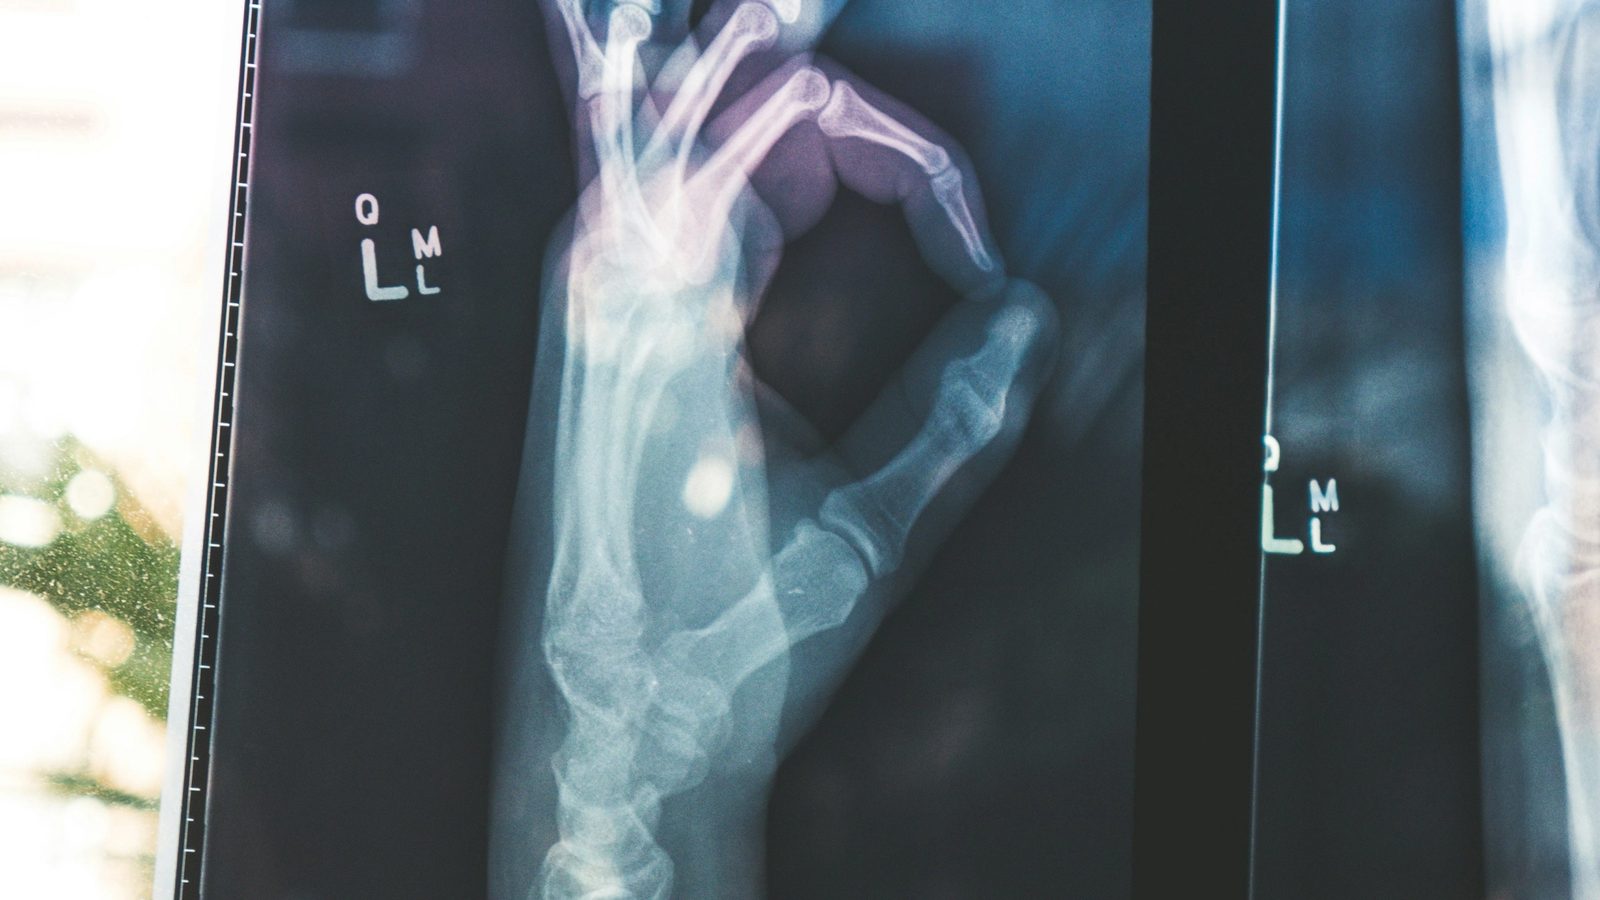

What comes to mind when you hear "medical technology?" Some amazing innovations have completely changed how we prevent, diagnose and treat diseases over the last century. From the X-ray that lets doctors see our bones to artificial joints that restore mobility, modern medicine would be unrecognizable without tech.

X-rays were actually discovered accidentally in 1895 by Wilhelm Röntgen playing with a cathode ray tube. By noticing a fluorescent glow, he realized a new type of ray was being emitted that could produce images of the inside of the human body without surgery! This simple discovery paved the way for today's digital radiography systems.

When something does go wrong with our health, the first step is pinpointing the problem through medical testing and diagnostic tools. We're probably all familiar with techniques like X-rays, CT scans, MRIs that use radiation or magnets to capture images of what's happening inside our bodies.